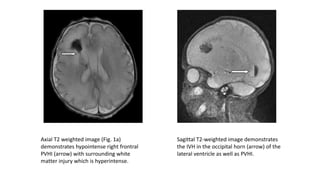

Periventricular Hemorrhagic Infarction

• Intraventricular hemorrhage can ca use m ass effect, resulting in obstr

uction of veno us o u tflo w fro m periventricular parenchymal tissue and

culminating in hem orrhagic infarction 35 secon d ary to veno us

hypertension.

• While PVHI is detectable on cranial sonography, MR imaging is more

sensitive than ultrasound in the detection and quantification of PVHI.

• Conventional MR offers the advantage of differentiating hemorrhagic and

necrotic components of PVHI .

• T2-weighted sequences display hemorrhage as regions of low signal,

contrasted against the neighboring venous infarct which appears

hyperintense.

• The superior tissue differentiation of MR imaging allows for more precise

estimates of infarct size and location.

Axial T2 weighted image (Fig. 1a)

demonstrates hypointense right frontral

PVHI (arrow) with surrounding white

matter injury which is hyperintense.

Sagittal T2-weighted image demonstrates

the IVH in the occipital horn (arrow) of the

lateral ventricle as well as PVHI.